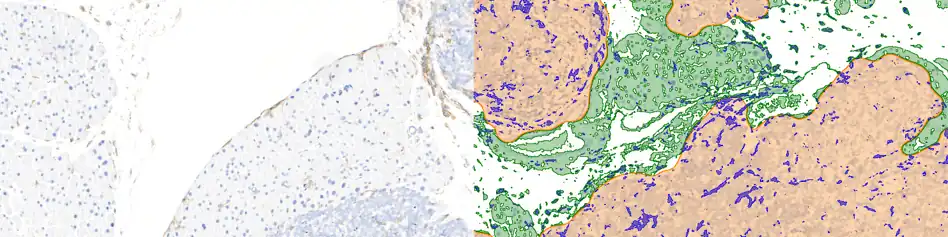

Tissue image cytometry or tissue cytometry is a method of digital histopathology and combines classical digital pathology (glass slides scanning and virtual slide generation) and computational pathology (digital analysis) into one integrated approach with solutions for all kinds of diseases, tissue and cell types as well as molecular markers and corresponding staining methods to visualize these markers. Tissue cytometry uses virtual slides as they can be generated by multiple, commercially available slide scanners, as well as dedicated image analysis software – preferentially including machine and deep learning algorithms.[1] Tissue cytometry enables cellular analysis within thick tissues, retaining morphological and contextual information, including spatial information on defined cellular subpopulations.[2]

In this process, a tissue sample, either formalin-fixed paraffin-embedded (FFPE) or frozen tissue section, also referred to as “cryocut”, is labelled with either immunohistochemistry[3](IHC) or immunofluorescent markers, scanned with high-throughput slide scanners and the data gathered from virtual slides is processed and analyzed using software that is able to identify individual cells in tissue context automatically and distinguish between nucleus and cytoplasm for each cell.[1] Additional algorithms can identify cellular membranes, subcellular structures (like cytoskeletal fibers, vacuoles, nucleoli) and/or multicellular tissue structures (glands, glomeruli, epidermis, or tumor foci).[4]Fluorescence Activated Cell Sorting (FACS) is a method of analysis that measures fluorescence signals on single cells, where the signal comes from antibody-mediated staining techniques and phenotypes detected by flow cytometry.[5] The major limitation of flow cytometry is that it can only be applied – as the name suggest – to cells in solution. Although methods of “solubilizing” solid tissue exist, any such processing irrevocably destroys the tissue architecture and any spatial context. Hence, tissue cytometry complements the use of flow cytometry and fluorescence microscope[6] in basic research, clinical practice, and clinical trials by providing FACS-like analyses on solid tissue sections (as well as adherent cell cultures) in situ. The advantage of tissue cytometry against flow cytometry is that tissue cytometry does not require the cells to be suspended in fluid, aiding in maintaining the integrity of the tissue structure, morphology, and contextual information, further assisting in precise and accurate contextual analysis that are not possible in flow cytometry.

A more robust and automated system was designed to perform flow cytometry-like analyses on immunostained cells in a fixed tissue and termed tissue cytometry.[7] The technique was introduced in the 1990s based on patents by Steiner and Ecker,[8] describing a procedure for “Cytometric Analysis of Diverse Cell Populations in Tissue Sections or Cell Culture Visualized Through Fluorescence Dyes and/or Chromogens". Tissue cytometry emerged as a transformative extension of digital pathology, promising to bridge the gap between image-based analysis and quantitative, data-driven insights. At its core, tissue cytometry enables the automated and quantitative analysis of cellular and tissue features. By employing computational algorithms and machine learning models, it can accurately segment nuclei, identify cell types, and quantify protein expression levels within the tissue context.

By precisely delineating individual nuclei, researchers can extract valuable information about nuclear size, shape, and texture, which can be correlated with various pathological conditions. Similarly, tissue segmentation algorithms enable the identification of different tissue compartments, such as tumor, stroma, and immune infiltrate, facilitating the analysis of spatial relationships between cellular components.[13]